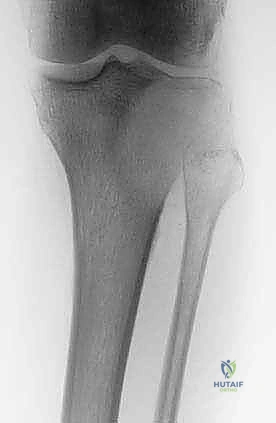

الخطوة الخامسة: إعادة البناء والترميم (Reconstruction)

بعد القضاء على الورم، يتبقى تجويف فارغ داخل العظم. يقوم الدكتور هطيف بملء هذا الفراغ إما باستخدام ترقيع عظمي (Bone Graft) أو الإسمنت العظمي (PMMA - Bone Cement). الإسمنت العظمي له فائدة مزدوجة: فهو يوفر دعماً ميكانيكياً فورياً للعظم، والحرارة الناتجة عن تصلبه توفر تأثيراً إضافياً قاتلاً للخلايا الورمية المتبقية.